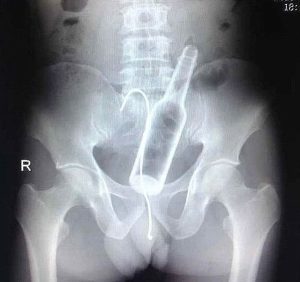

Doktora görün, tahlilleri yaptır, röntgenleri çektir falan filan derken insanın ömründen yaşam gider. Gelin görün ki bu sefer çektirilen röntgenlerde öyle ilginç şeyler çıkmış ki ağzımız açık kaldı…